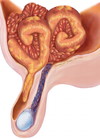

O que passa pelo canal inguinal no homem?

O que contém essa estrutura?

FUNÍCULO ESPERMÁTICO

O que passa pela canal inguinal na mulher?

Ligamento redondo do útero